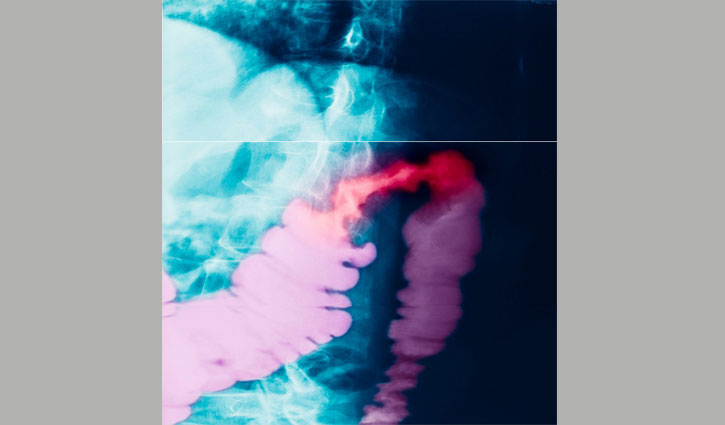

এই ছবিটি কোলন ক্যানসারে আক্রান্ত এক রোগীর এক্স-রে। এ ধরনের ক্যানসার মূলত টিউমার এর কোষ এর অস্বাভাবিক বৃদ্ধির ফলে ঘটে থাকে। এই ক্যানসার প্রথমে কোনো উপসর্গ নাও দেখাতে পারে কিন্তু টিউমারের বৃদ্ধি শরীরের খাদ্য হজমে ব্যাঘাত ঘটাতে পারে।